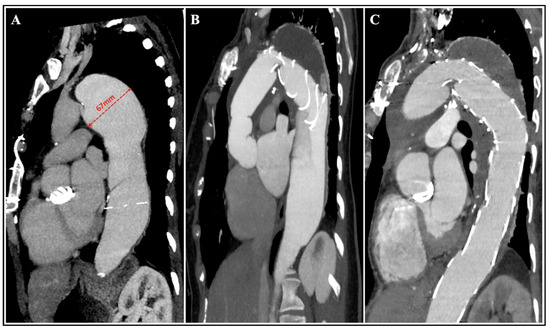

2. FET Technique: General Considerations

3.2. Chronic Aortic Dissection